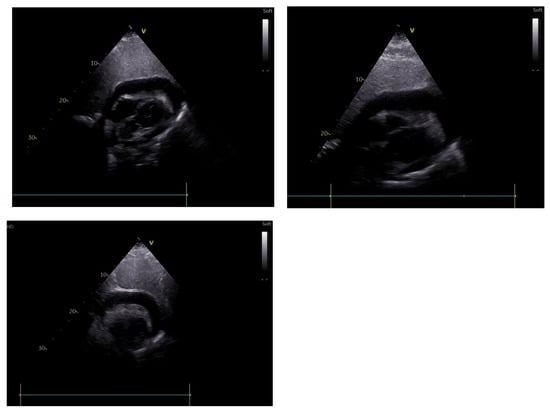

At the end of the second week, the patient was diagnosed with Cl. difficile enterocolitis and was treated with oral metronidazole (500 mg every eight hours) and vancomycin (250 mg every six hours) for 12 days. Subsequently, he developed dyspnea, ascites, peripheral edema, and hypotension. Echocardiography revealed pericardial constriction, compression of both ventricles, a respiration-related intraventricular septal shift towards the left ventricle, marked respiratory variation in mitral and tricuspid inflow velocities (mitral Doppler velocity with an inspiratory decrease of 27% and tricuspid Doppler velocity with an increase of 33%), and an increase in the hepatic vein expiratory diastolic reversal flow (Figure 5).

Figure 5. Markedly decreased left ventricular diastolic diameter from long axis parasternal view within 20 days.